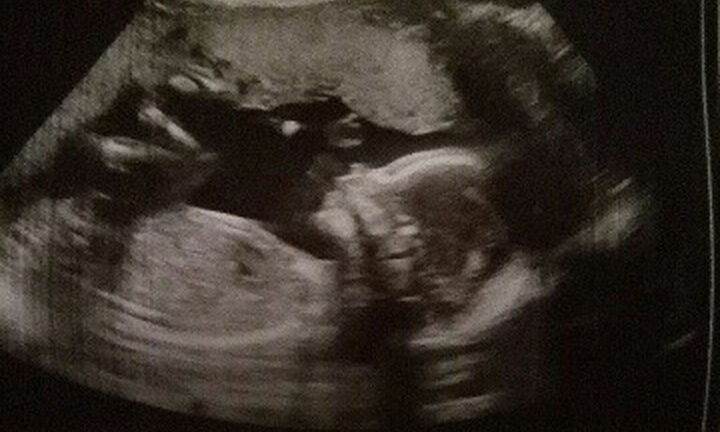

Krista Schwab, người phụ nữ có 2 tử cung, 2 âm chia sẻ, cô đã tưởng rằng, mình không bao giờ có thể có con, tuy nhiên, phép màu tuyệt vời đã đến với vợ chồng cô.